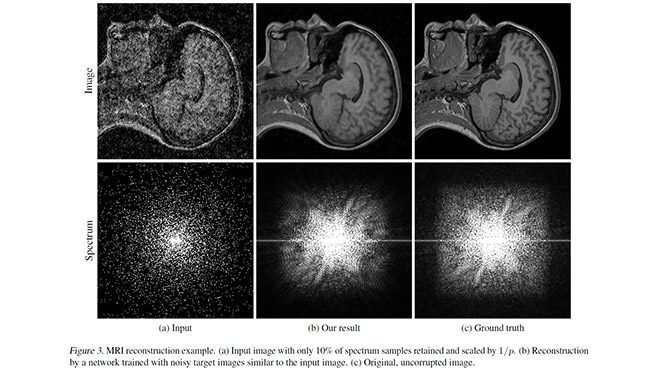

Ekran kartı pazarının yıldız ismi Nvidia, son dönemde gerçekten çok ciddi araştırmalar yapıyor. Bunlardan birisine daha imza atan firma, bu sefer yine fotoğraflara odaklanıyor. MIT ve Aalto Üniversitesi’nin yardımıyla geliştirilen yeni yapay zeka, “Noise2Noise” olarak isimlendiriliyor. Bu yapay zeka yüksek kumlamaya sahip fotoğrafları tam anlamıyla tertemiz hale getiriyor. Bunu fotoğrafların temiz haline ihtiyaç duymadan yapan yapay zeka, gerçekten çok iyi sonuçlar ortaya koyuyor. Yaklaşık 50 bin fotoğraf ile eğitilmiş bir makine öğrenme altyapısı üzerine kurulan Noise2Noise, fotoğrafları oldukça derinlemesine inceliyor ve kumlama haricinde oluşan bozulmaları da giderebiliyor. Sadece gündelik fotoğraf çekimleri değil MRI görüntüleri için de işe yarayan sistem, büyük getiriler sunuyor.